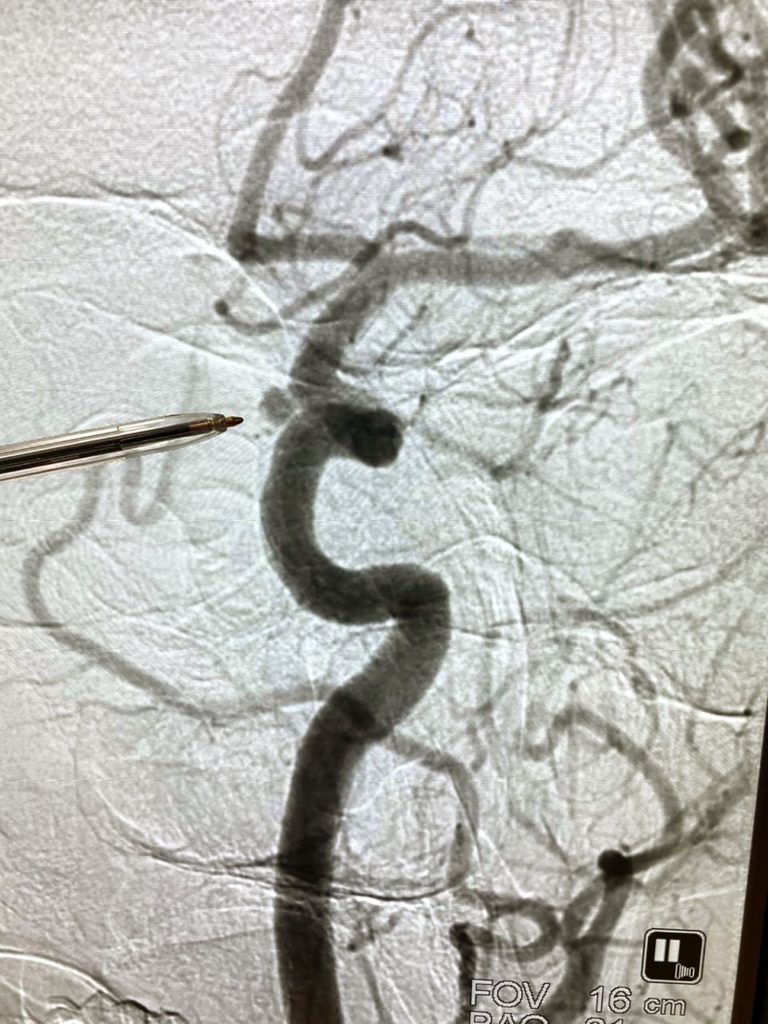

Слева: в госпитале МЧС. Справа: этот кадр был сделан в кабине лифта в больнице. Лечение закончилось, и Леша отправляется на реабилитацию Фото: Александра Михайлова Фотография сосудов головного мозга Алексея. Ручкой врач указывает место, где была локализована аневризмаФото: Александра Михайлова

В голове Алексея разорвалась аневризма — маленький пузырек на сосуде. Это и привело к кровоизлиянию и инсульту. Алексею сделали операцию для восстановления поврежденного сосуда. На десятые сутки после такой операции пациент может впасть в кому, поэтому нужно принимать сильные препараты, чтобы это предотвратить. Но из-за них восприятие реальности тоже изменяется.